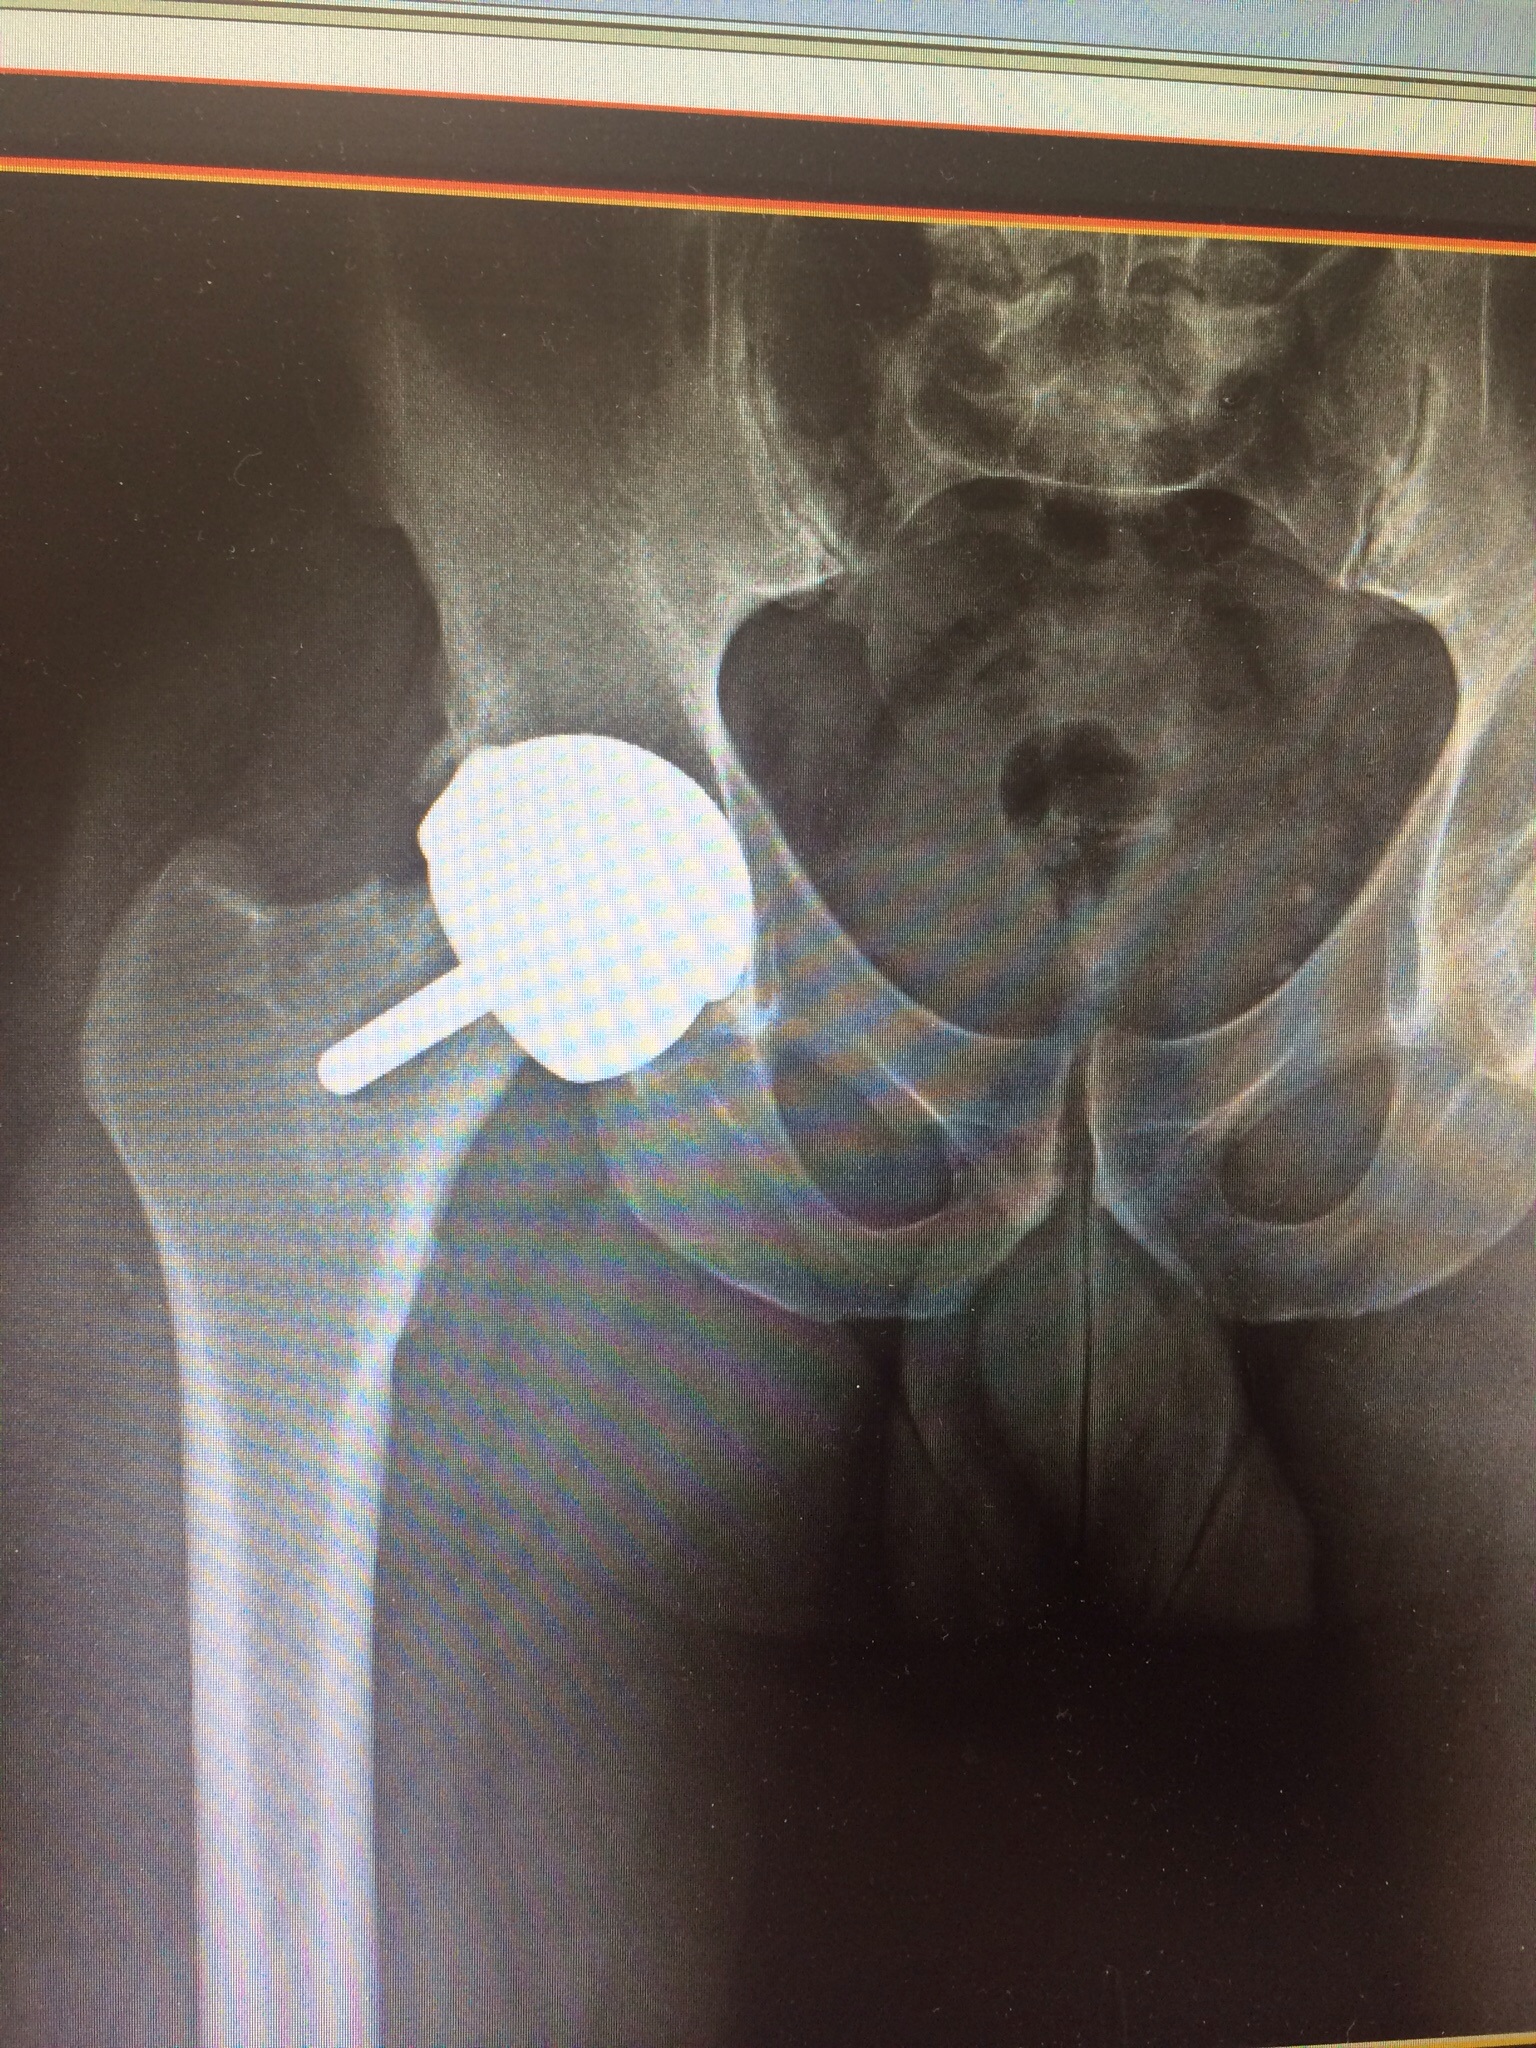

My hip resurfacing has failed. So back in for a revision. June 4th 2015